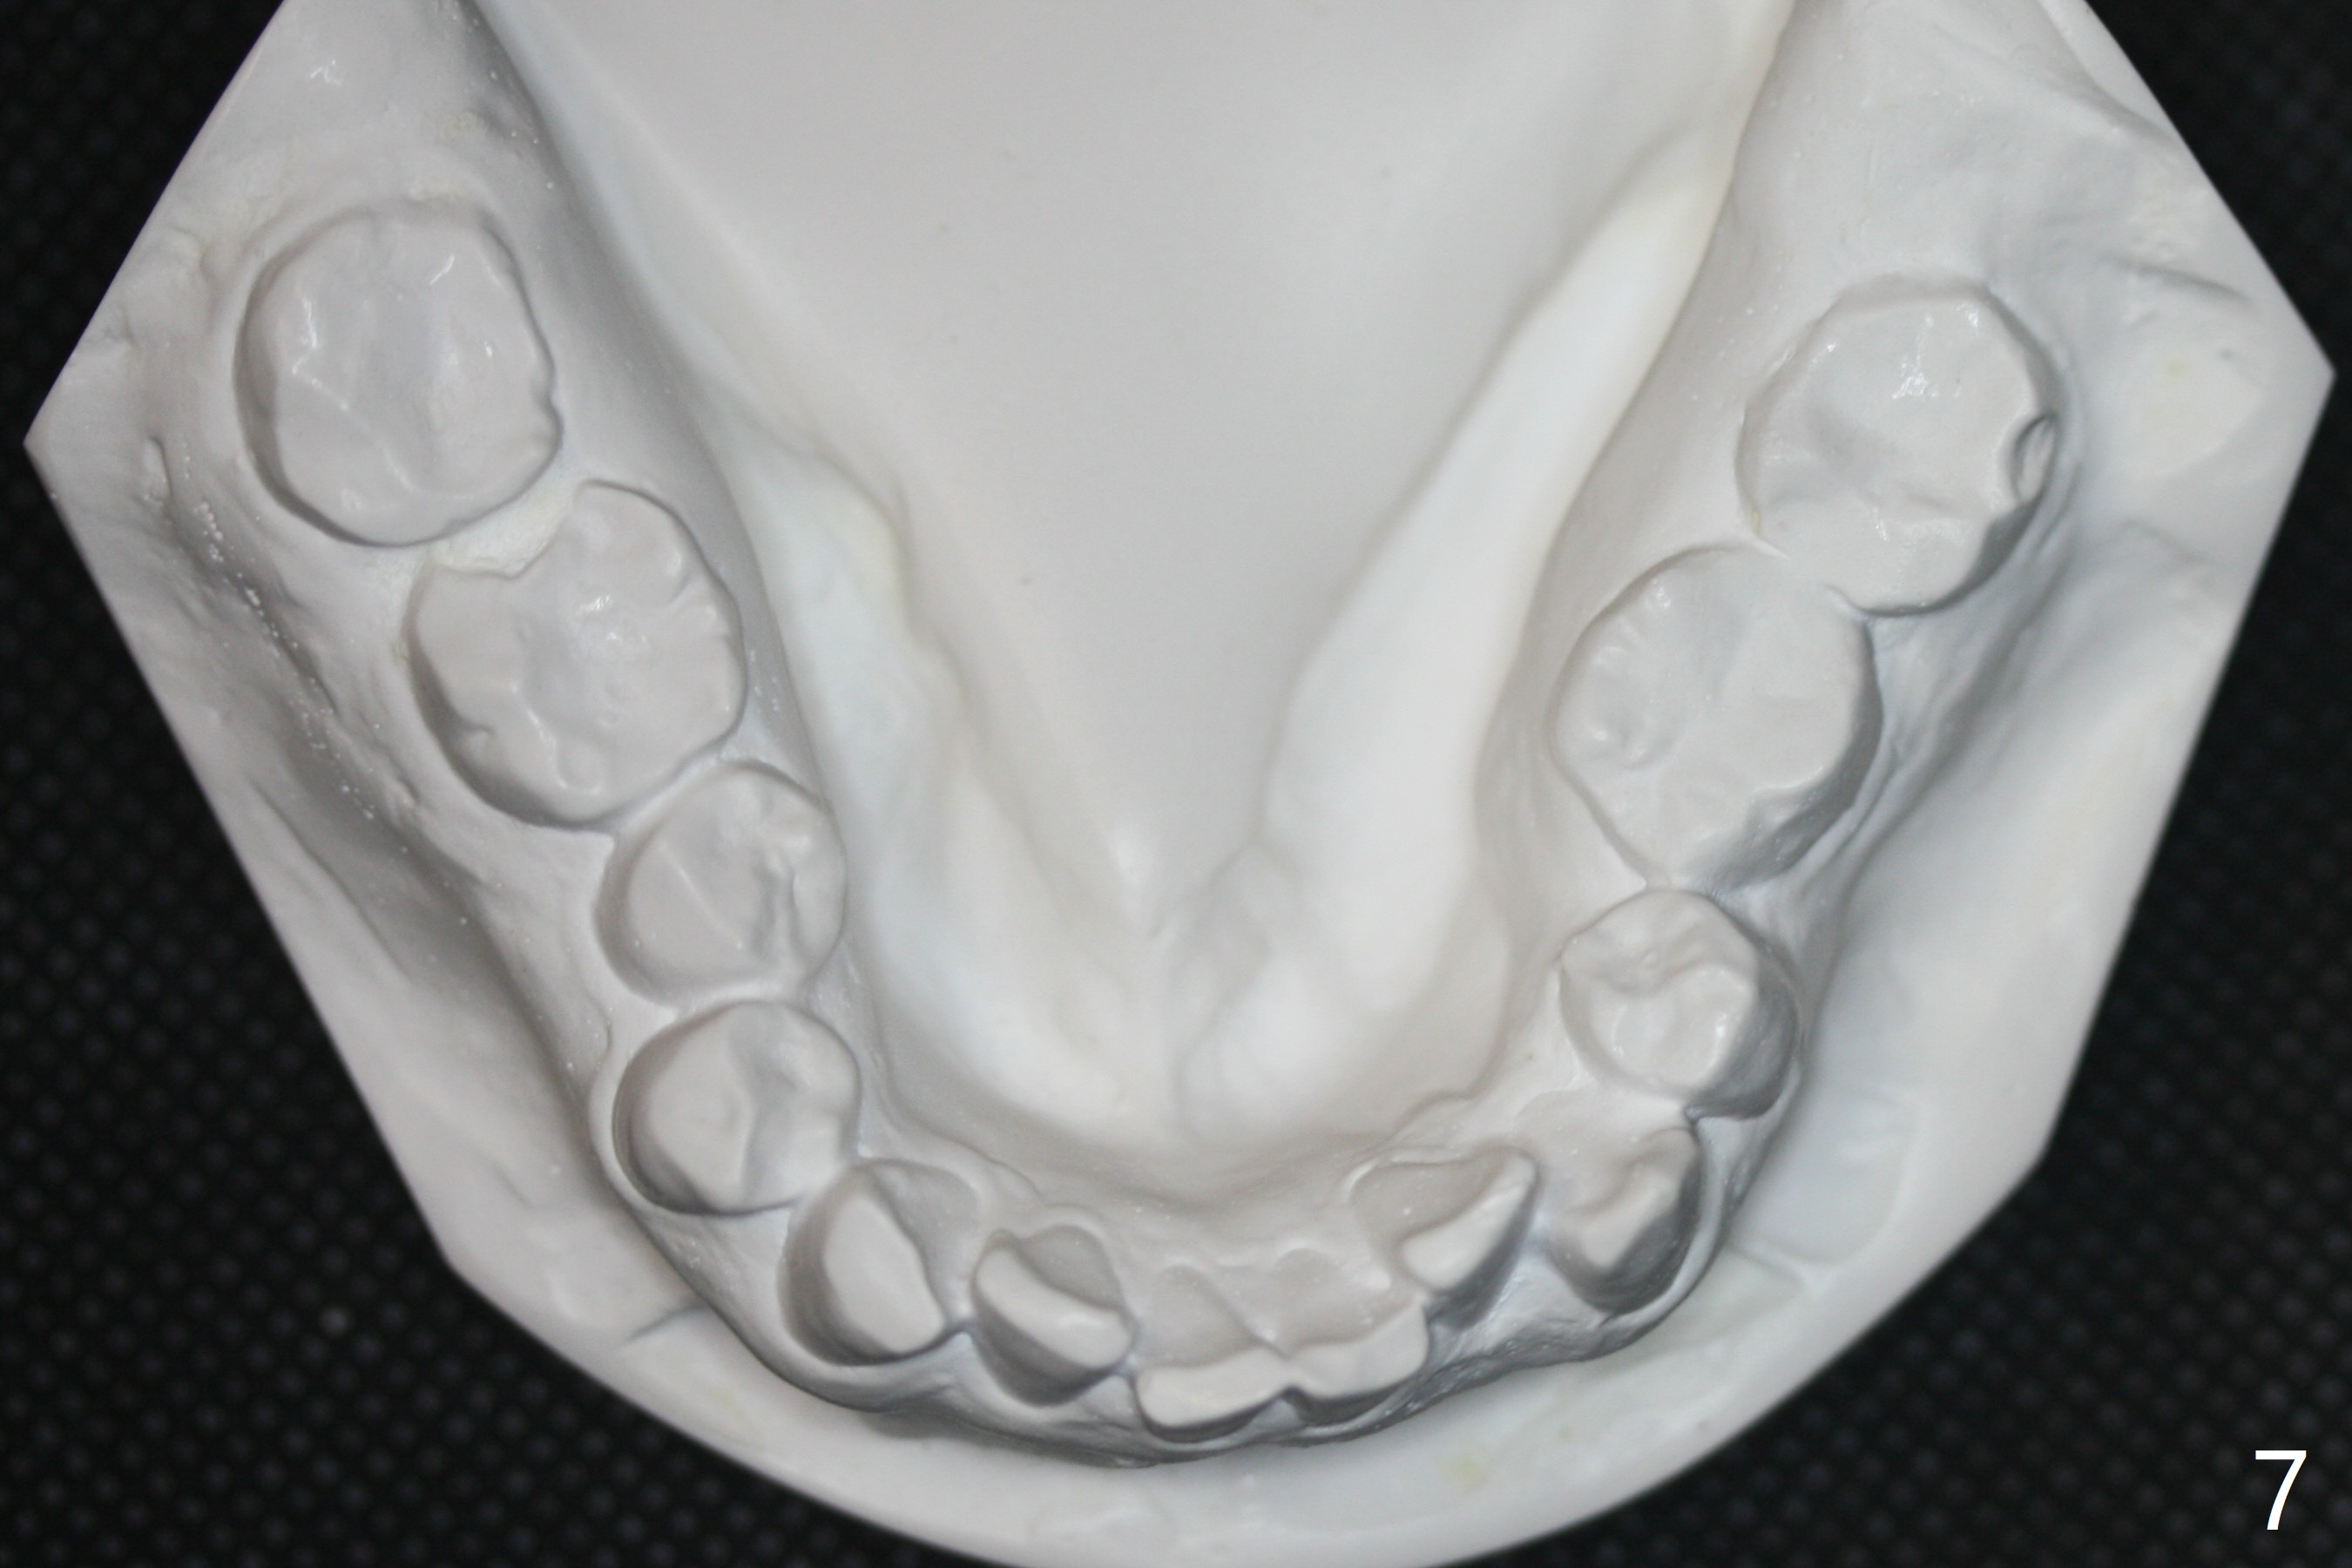

In fact impression for models (Fig.3-7) is taken after UL caries control.  Sedative filling is done at UL1,3 (Fig.6 *) and definitive restoration will be done when crowding resolves.  The defects at UL6,7 (Fig.6 x) is so extensive that after composite molar bands are placed immediately for retention.  Amazingly, there is no symptom after UL6,7 restoration.  Therefore UL4 will be extracted for crowding resolution.  UR 5 (Fig.1-3,6) has been extracted, while LR5 (Fig.2,7) will be.